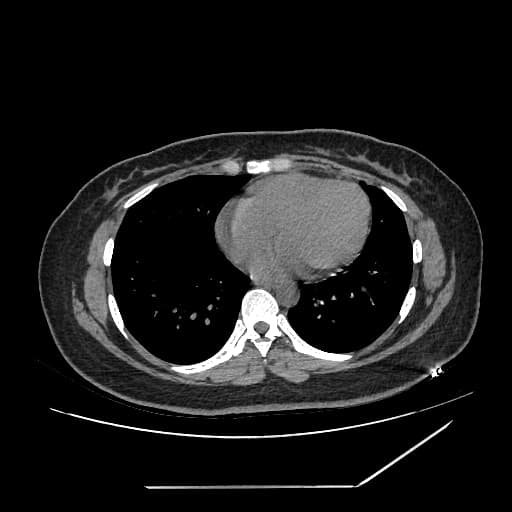

Axial C+ portal venous phase

Ca bệnhPerforated Meckel's diverticulum with enterolith

Perforated Meckel's diverticulum with enterolith

một cấu trúc hình ống, đầu tù được thấy xuất phát từ hồi tràng xa, phù hợp với túi thừa Meckel.

túi thừa dày thành, tăng mật độ, kèm theo mờ do viêm mô mỡ quanh và hạch mạc treo tăng kích thước.

một cấu trúc tăng mật độ, giới hạn rõ nằm tại cổ túi thừa, phù hợp với sỏi ruột.

dịch tự do và khí ngoài lòng ruột quanh túi thừa, gợi ý thủng khu trú.

tổn thương viêm lan tỏa do tiếp xúc tại đại tràng lên và nửa đoạn gần đại tràng ngang.

phần thừa manh tràng (cecal appendix) bình thường.

không thấy dấu hiệu tắc ruột non.

Meckel's diverticulum thủng kèm enterolith